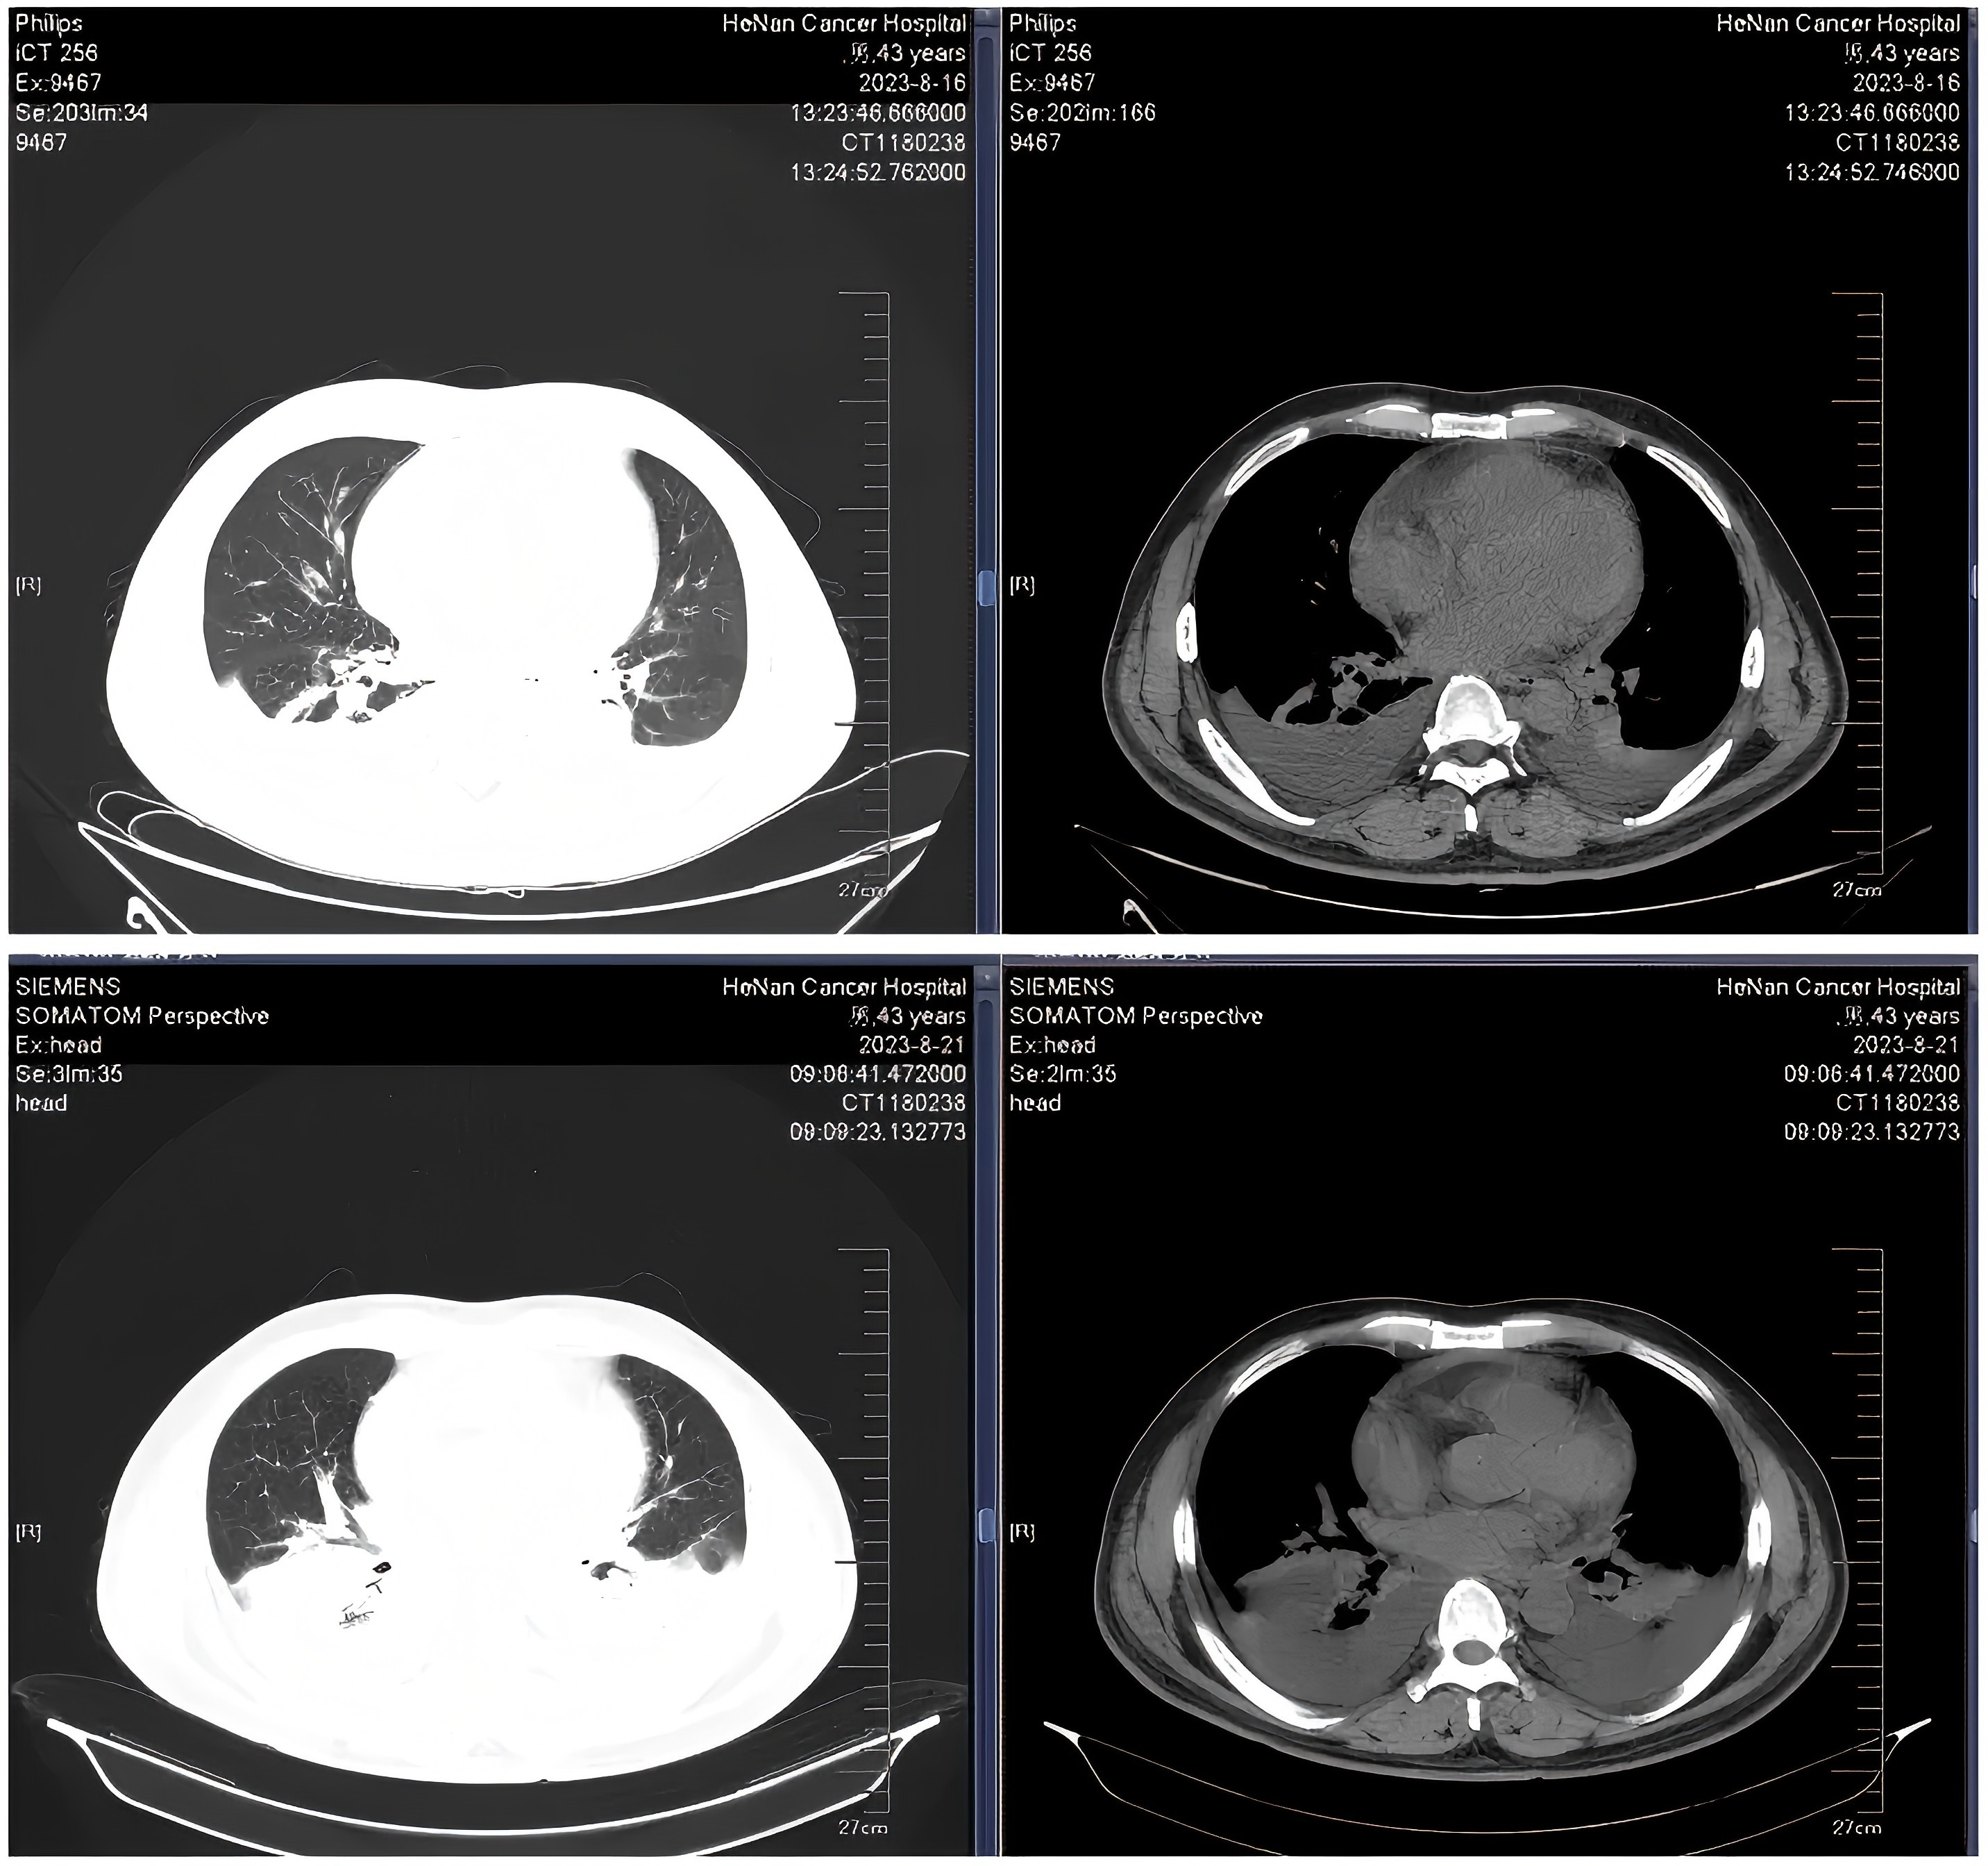

入院时患者合并新型冠状病毒感染,伴持续高热及严重肺部感染,基础状况较差,无法耐受标准化疗(图1)。2023年7月27日起予VA方案(Ven每日递增至400mg,阿扎胞苷100mg d1~7)诱导治疗。第15天复查骨髓提示原始细胞降至10.5%,多参数流式细胞术(FCM)检测到可测量的微小残留病灶(MRD),其中异常原始细胞占4.9%。治疗期间合并持续高热、重症肺炎及胸腔积液,经积极抗感染及支持治疗后病情控制。